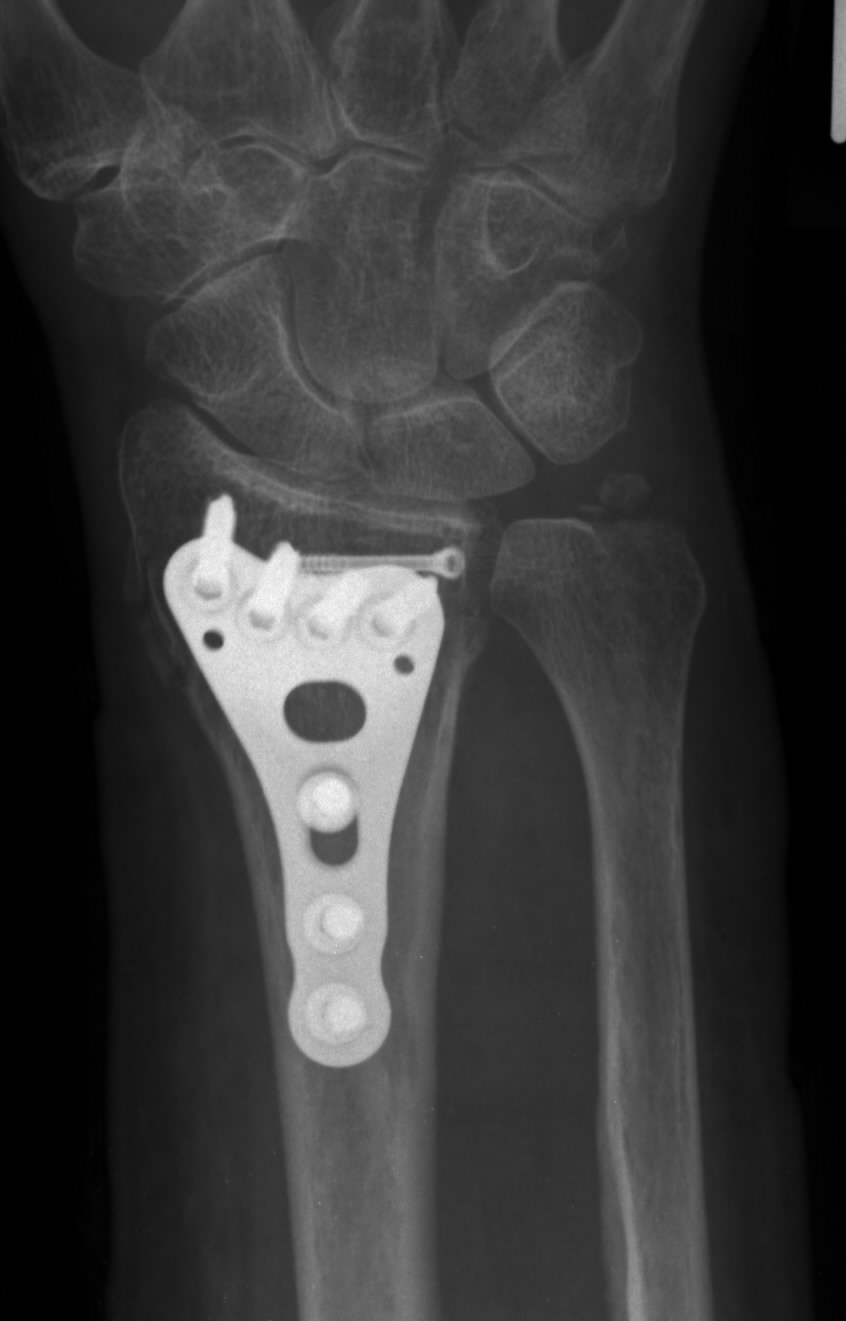

Es ist wichtig, schmerzhafte Schrauben oder Platten im Knochen zu erkennen und zu diagnostizieren. Da Knochenbrüche häufig bei Unfällen passieren, sind in vielen Fällen Erste-Hilfe-Massnahmen notwendig.Die Prognose bei einem Knochenbruch richtet sich nach dem Ort, der Art und dem Ausmaß der Schäden sowie natürlich nach der entsprechenden Therapie. Die Wunde wird mehrfach mit Kochsalzlösung gespült. Differentialdiagnose.Bei Kindern muss das Material, da das Knochenwachstum noch nicht abgeschlossen ist, nach Abschluss der Knochenheilung grundsätzlich entfernt werden. Sturzunfälle sind die häufigste Ursache von Knochenbrüchen. Bei der Untersuchung .

Die ersten Platten/Schraubenkonstruktionen sind von Carl Hansmann in Hamburg 1886 beschrieben.Nach der Diagnose eines Knochenbruchs muss der Arzt zunächst beurteilen, ob der Bruch. Heilt die Fraktur nicht korrekt, können Fehlstellung en oder Stufenbildungen im Gelenk die Folge sein. Nach einer Sprunggelenksfraktur spüren alle Patienten sofort einseitig heftige Schmerzen und eine resultierende Instabilität beim Gehen und Stehen.medizinische-hausmittel.So unterstützen Sie die Heilungsdauer nach dem Knöchelbruch. Komplikationen. Die Therapie eines Knochenbruches besteht im Allgemeinen . Schwellungen und große Schmerzen sind die Folge. Ursache ist eine übermäßige Drehung des Knochens.RippenbruchHandgelenkbruchSchlüsselbeinbruch

Kurzinformationen. eingeschränkte Funktion bzw. Warum verwenden wir vorzugsweise winkelstabile Implantate zur Behandlung eines Knochenbruches? Die . Ein Bruch (Fraktur) ist ein Anriss oder Bruch eines Knochens. Befindet sich die Person in einem Gefahrenbereich, sollte sie, wenn irgendwie möglich, zuerst aus diesem entfernt werden. Winkelstabile Implantate zur Knochenbruchbehandlung.Allgemeine Informationen und Prinzipien. Sobald die schmerzhaften Schrauben identifiziert sind, gibt es verschiedene . Schonhaltung eines Körperteils. Untersuchung von Nervenverletzungen, Gefühlsstörungen oder Lähmungen.Die ersten Wochen nach Auftreten der Fraktur sollten ruhig angegangen werden, körperliche Anstrengung beschränkt werden. Die Patienten leiden unter dauerhaften Schmerzen und Bewegungseinschränkungen. Knochenbrüche könnten konservativ, mittels Ruhigstellung (Schiene oder Gips), oder operativ behandelt werden. Schon in der Entlastungsphase beginnen isometrische Kräftigungsübungen aus der Krankengymnastik, das Verhindern vom Masseabbau der Muskulatur. Ursache ist eine direkte oder indirekte Gewalteinwirkung von außen. Nur bei offenen, verschobenen oder komplexen Frakturen oder zusätzlichen Gefäßverletzungen sowie bei Brüchen an den Enden des Knochens kommt die konservative Therapie an ihre Grenzen.